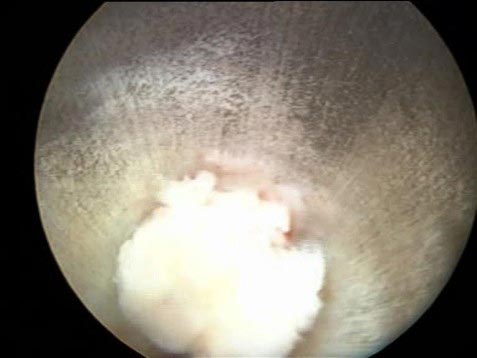

Το ενδοκαναλικό κομμάτι του μεσοσπονδυλίου δίσκου όπως φαίνεται με το ενδοσκόπιο μέσα στον αυλό εργασίας (working sleeve) και τη στιγμή της εξόδου όπως φαίνεται από την κάμερα

Το τεμάχιο του δίσκου φτάνει σε μήκος τα 3 εκατοστά!